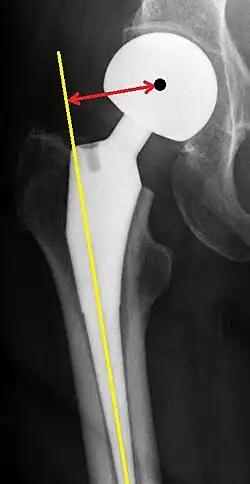

Post-operative projectional radiography is routinely performed to ensure proper configuration of hip prostheses.

The direction of the acetabular cup influences the range of motion of the leg, and also affects the risk of dislocation.[16] For this purpose, the acetabular inclination and the acetabular anteversion are measurements of cup angulation in the coronal plane and the sagittal plane, respectively.

![Leg length discrepancy after hip replacement is calculated as the vertical distance between the middle of the minor trochanters, using the acetabular tear drops[95] or the transischial line[16] as references for the horizontal plane. A discrepancy of up to 1 cm is generally tolerated.[95][16]](./Leg_length_discrepancy_after_hip_replacement.jpg)

Center of rotation: The horizontal center of rotation is calculated as the distance between the acetabular teardrop and the center of the head (or caput) of the prosthesis and/or the native femoral head on the contralateral side.[95] The vertical center of rotation instead uses the transischial line for reference.[95] The parameter should be equal on both sides.[95]